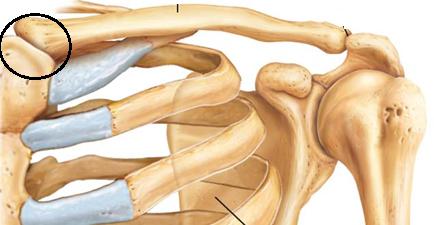

Ключица — небольшая, S-образно изогнутая трубчатая кость, которая одним концом соединяется с грудиной (грудино-ключичный сустав), а вторым концом — с акромиальным отростком лопатки (акромиально-ключичный сустав). Традиционно в ключице выделяют три части: грудинный конец, диафиз (средняя часть) и акромиальный конец.

Основные травмы ключицы — это переломы и вывихи. Поскольку у ключицы два конца (акромиальный и ключичный) то и вывихи могут быть как акромиального, так и грудинного конца. Чаще бывают вывихи акромиального конца. К ключице прикрепляется несколько связок, которые соединяют ее с лопаткой.

Классический пример травмы, при которой происходит вывих акромиального конца ключицы — падение на плечо. При этом рвутся связки, соединяющие ключицу и лопатку, и после этого, ключица под действием тяги мышц смещается кверху.

Конечно же, поскольку связок, прикрепляющихся к ключице несколько, то возможны различные варианты их разрывов. Например, может разорваться только капсула акромиально-ключичного сустава — в таком случае вывиха не произойдет или будет подвывих, поскольку ключицу будут держать другие связки. Если разорвутся другие связки (коническая и трапециевидная связки), произойдет уже вывих ключицы.